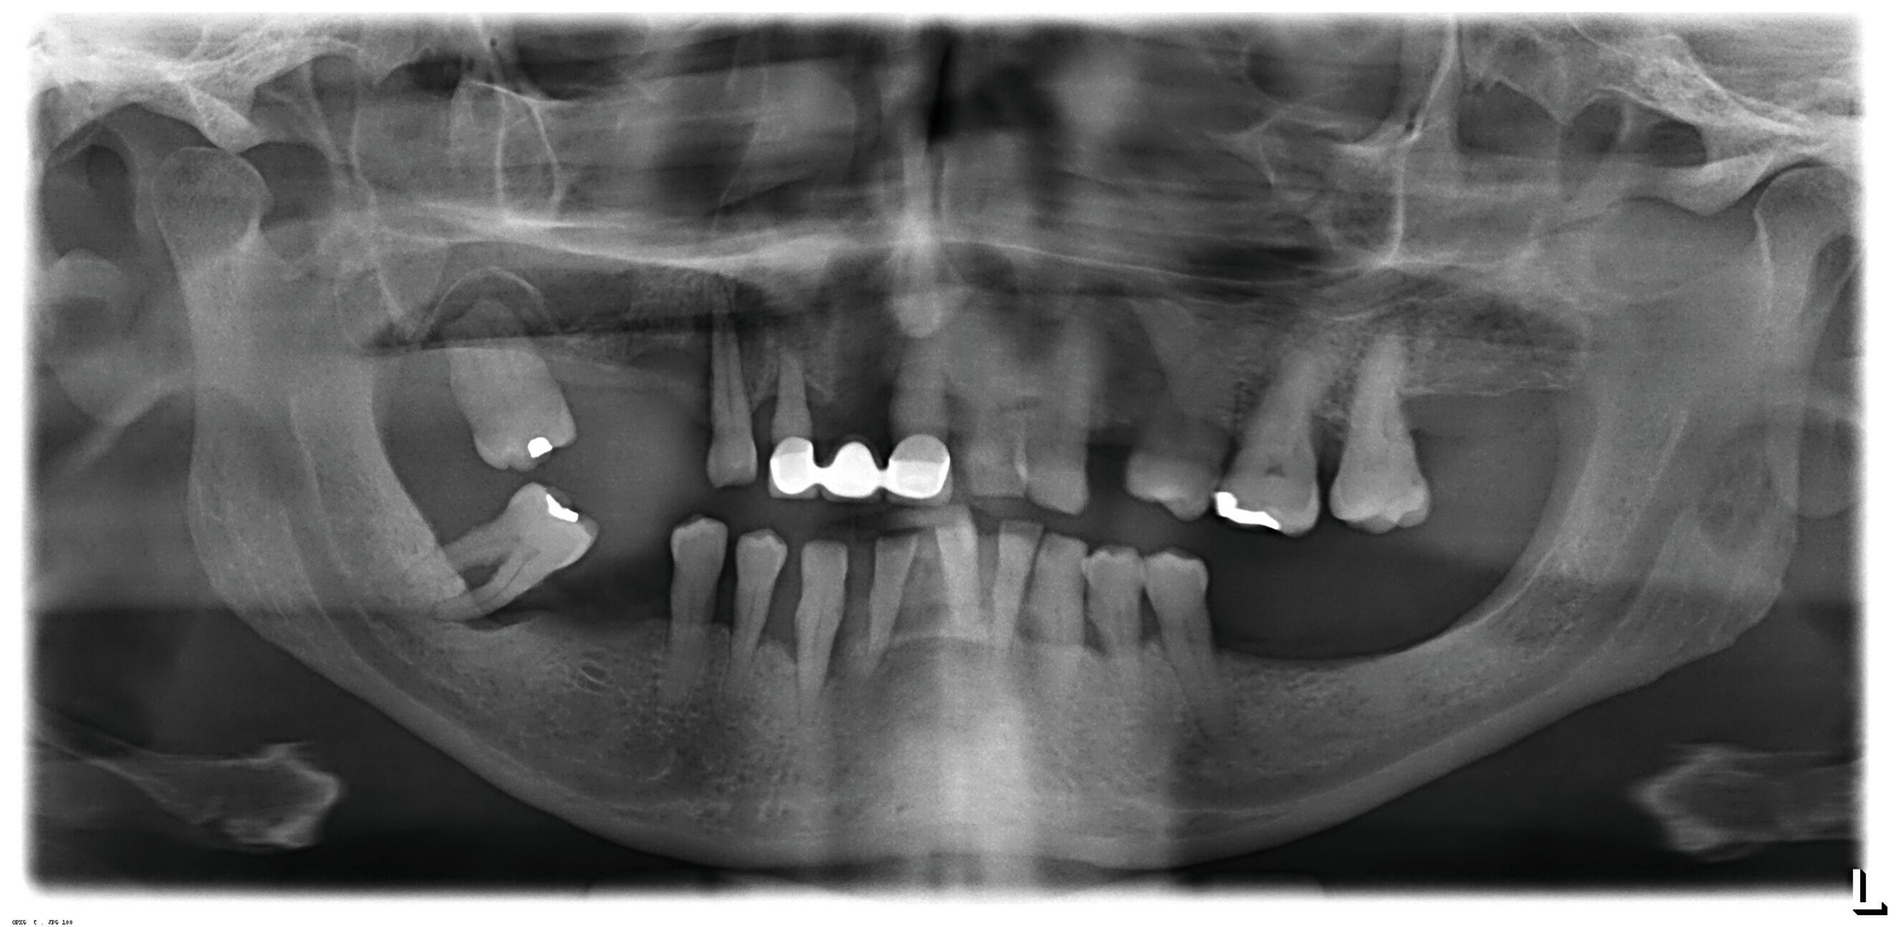

Ein 68-jähriger Mann stellte sich fußläufig in einem verwahrlosten und deutlich reduzierten Allgemeinzustand in der Notaufnahme des Evangelischen Krankenhauses Düsseldorf vor. Er berichtete bei gewisser Sprachbarriere über starke Schmerzen in der rechten Gesichtshälfte, die sich im Anschluss an eine Zahnentfernung entwickelt und im Verlauf verstärkt hätten. Vor sieben Tagen waren die Zähne 18, 14 und 48 extrahiert worden (Abbildung 2).

Laborchemisch offenbarte sich ein entgleister Diabetes mellitus mit einer Blutglukose von 507 mg/dl (HbA1c 11,4 Prozent) und diabetischer Ketoazidose (pH 7,15). Die Entzündungsparameter waren mit einer Leukozytenzahl von 18.000/µl und einem CRP von 30 mg/dl erhöht. Der Procalcitonin-Wert von 0,16 ng/ml sprach allerdings gegen eine bakterielle Infektion. Die Computertomografie des Schädels zeigte lediglich Resorptionen im Bereich der rechten Nasenhöhle und eine diskrete Volumenvermehrung des rechtsseitigen Wangen- und orbitalen Weichgewebes. Abszessformationen fanden sich, passend zum klinischen Befund, nicht (Abbildung 4).